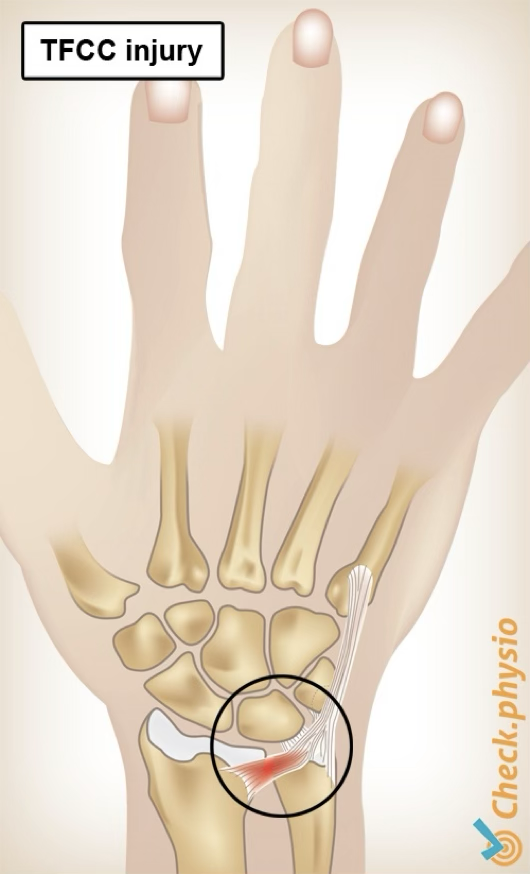

TFCC injury

Triangular fibrocartilage complex (TFCC) is a combination of ligaments and “meniscus” cartilage on ulnar side

Gets injured when patient has a violent twist of the wrist, typically with a hyperextension

TFCC injury symptoms

pain on ulnar side, possible clicking, lack of wrist extension, swelling

TFCC injury treatment

if suspected, should send to dr for images

may need splint for about 4 weeks (rest), then start with strengthening and ROM exercises (bad case may need surgery)